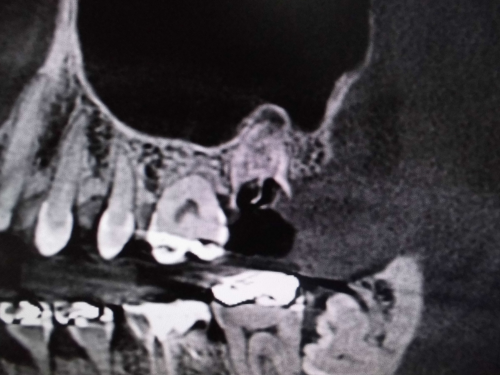

上顎洞との位置関係が確認できます。

CTでは近心の第二根管も確認できます。

原因が頬側近心根とわかりました。上顎洞粘膜が肥厚しているのもわかります。